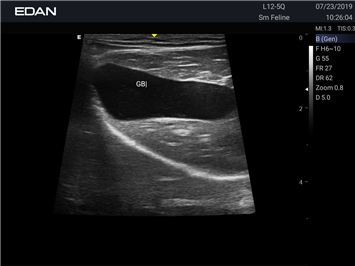

Ветеринарный ультразвук одним нажатием. Система Acclarix AX2 VET разработана с целью обеспечить бескомпромиссную производительность по доступной цене. Наличие уникальных двойных аккумуляторов в легком корпусе массой 4,5 кг из магниевого сплава позволяет системе Acclarix AX2 VET удовлетворять все потребности ветеринарных исследований, сохранив низкую стоимость.

EDAN Acclarix AX2 VET представляет собой специализированную ветеринарную ультразвуковую систему, сочетающую высокую производительность с доступной ценой. Благодаря продуманной конструкции и передовым технологиям, система обеспечивает качественную диагностику животных различных видов.

B-режим, Двухмерное сканирование:

Да

• Предустановленные протоколы для различных видов животных